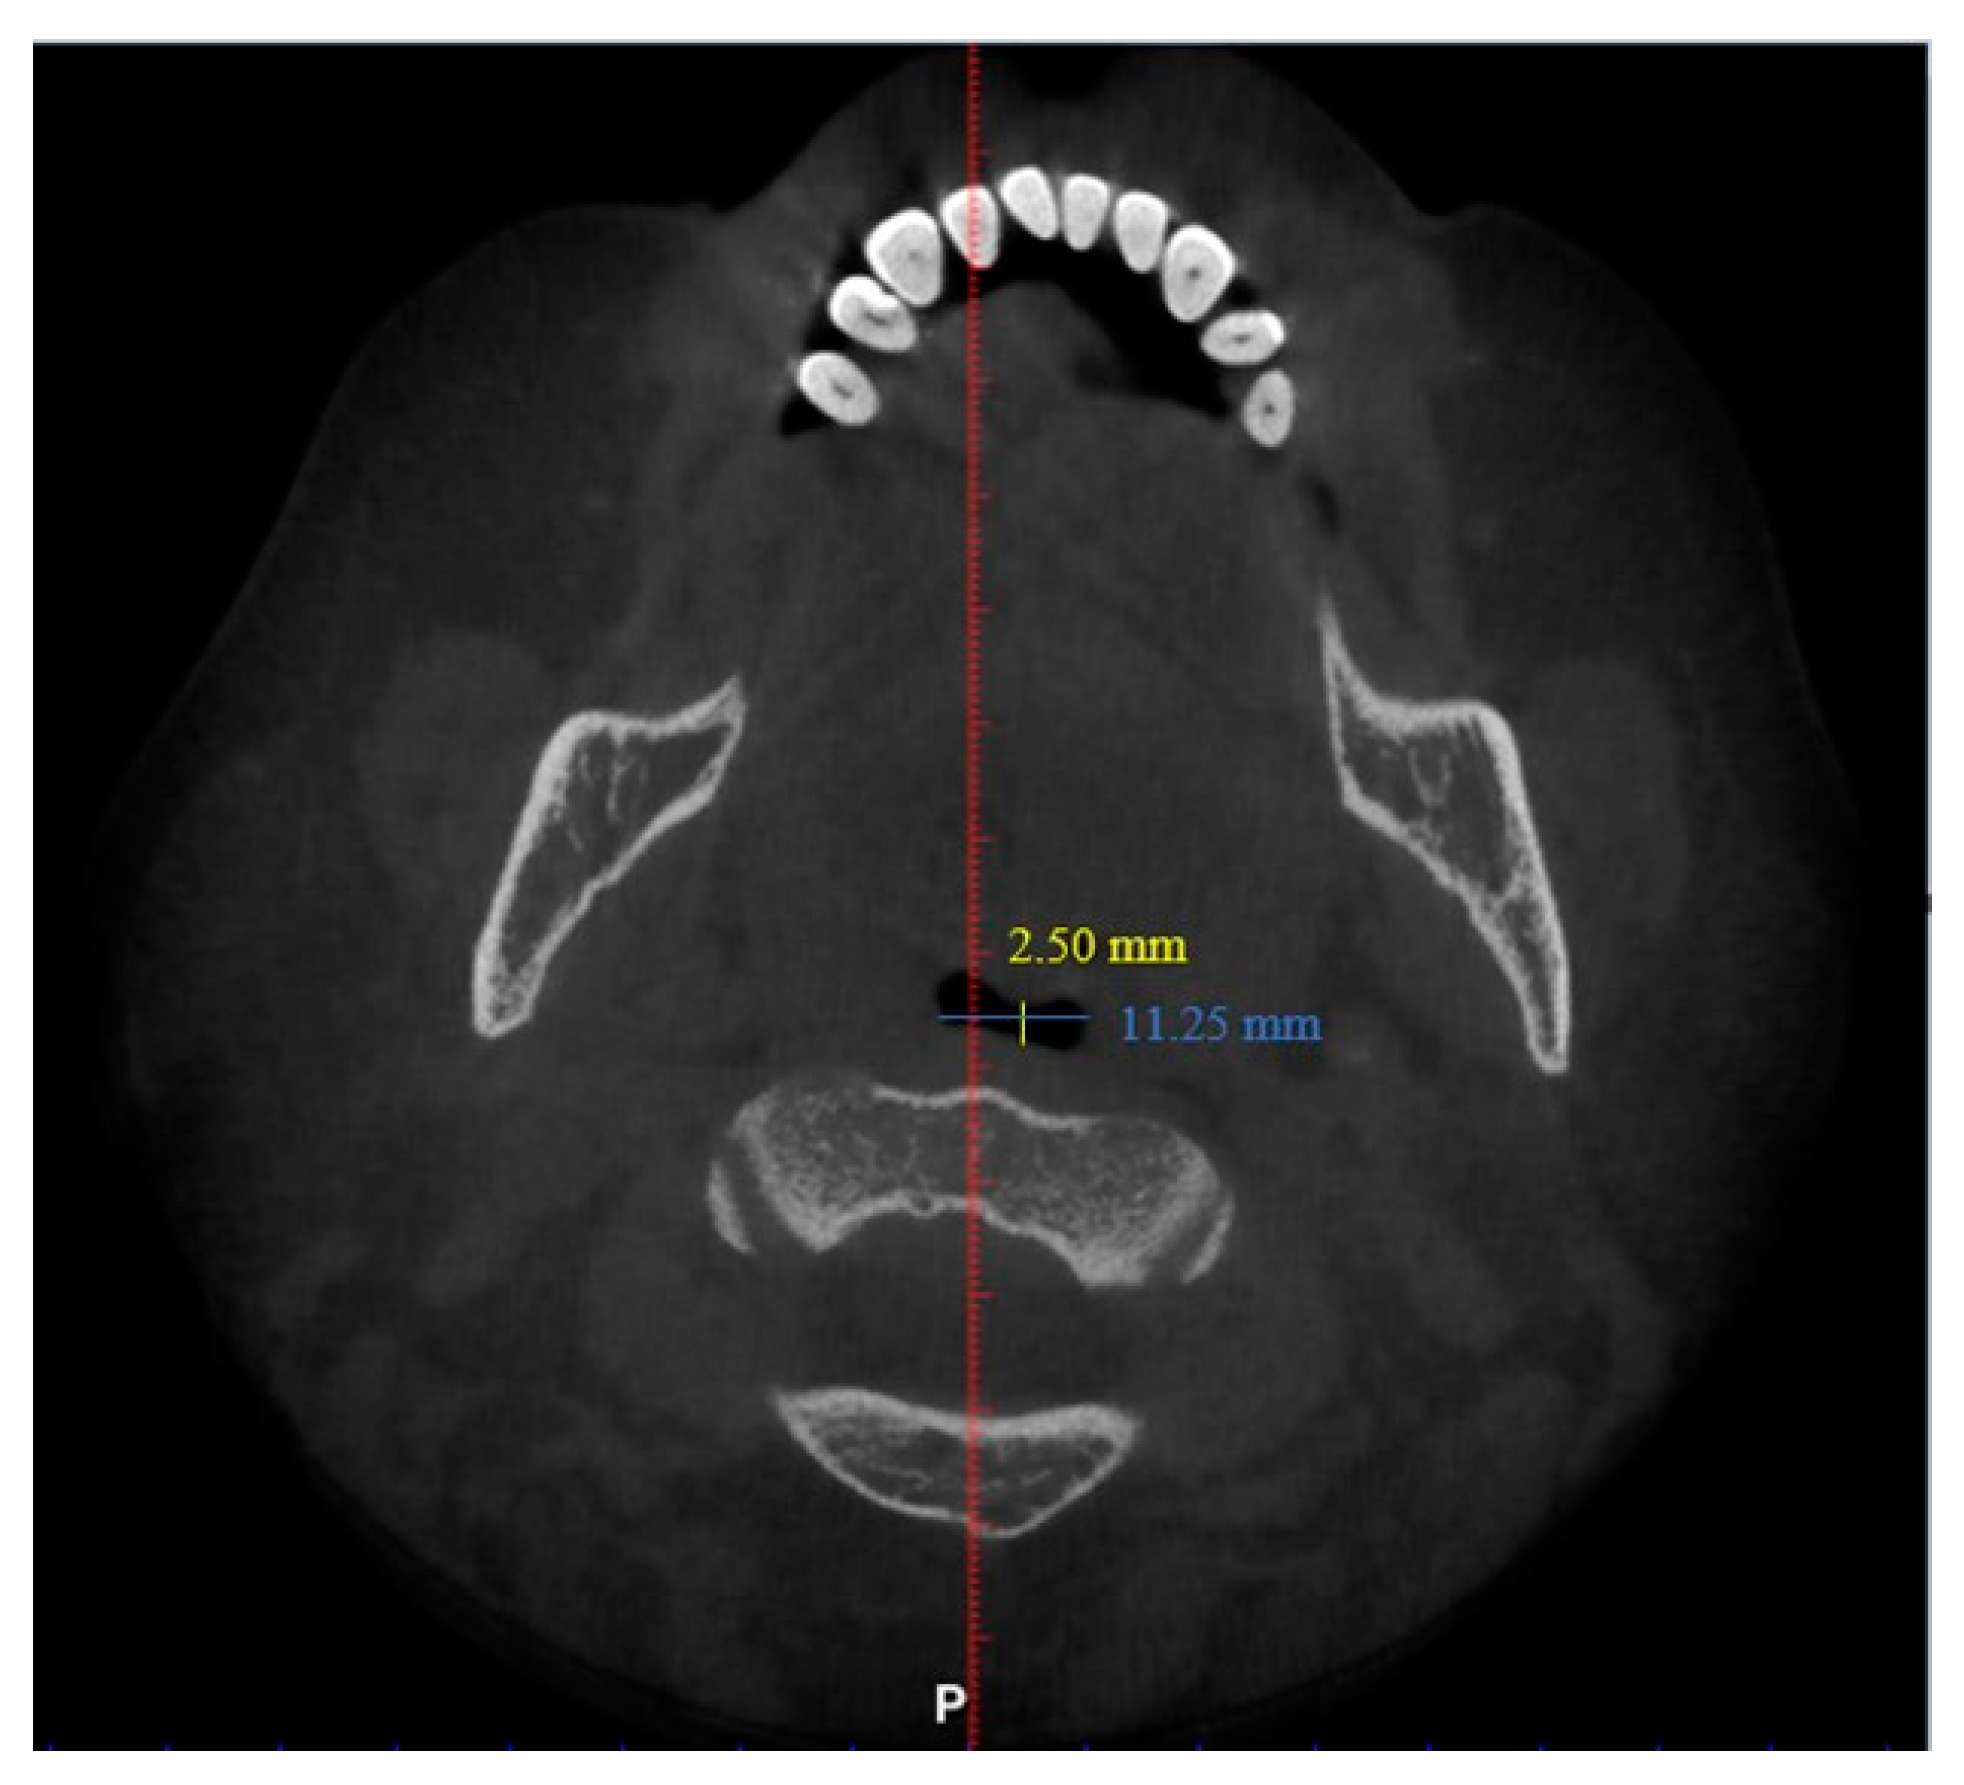

| N | Minimum | Maximum | Mean | Std. Deviation | |

| Length (mm) | 101 | 29.93 | 55.75 | 42.63 | 6.24 |

| Total volume (cm3) | 101 | 94.58 | 173.45 | 131.67 | 17.91 |

| Average volume (cm3) | 101 | 3.34 | 32.09 | 11.10 | 5.21 |

| Antero-posterior (mm) | 101 | 1.00 | 14.50 | 6.44 | 3.19 |

| Width (mm) | 101 | 8.00 | 37.00 | 21.69 | 6.54 |

| Valid N (listwise) | 101 |